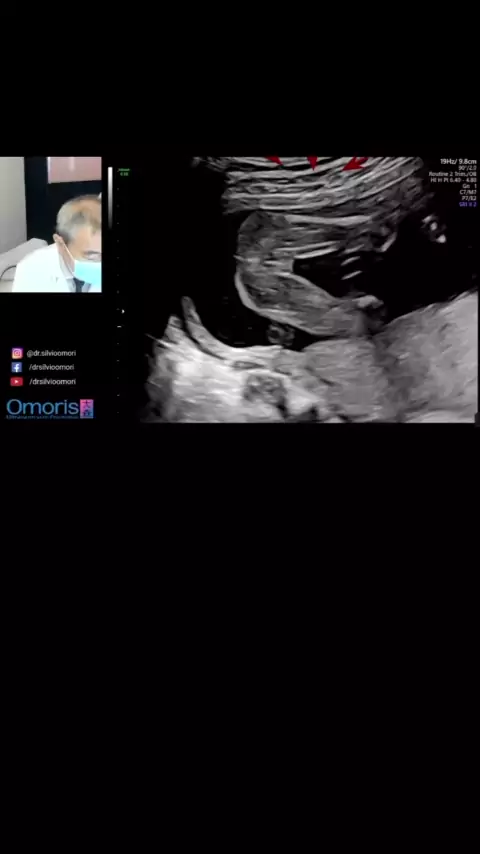

dr.silvioomori

Descobrindo sexo do bebê #gravida#bebe#meninooumenina #3D #ultrassom